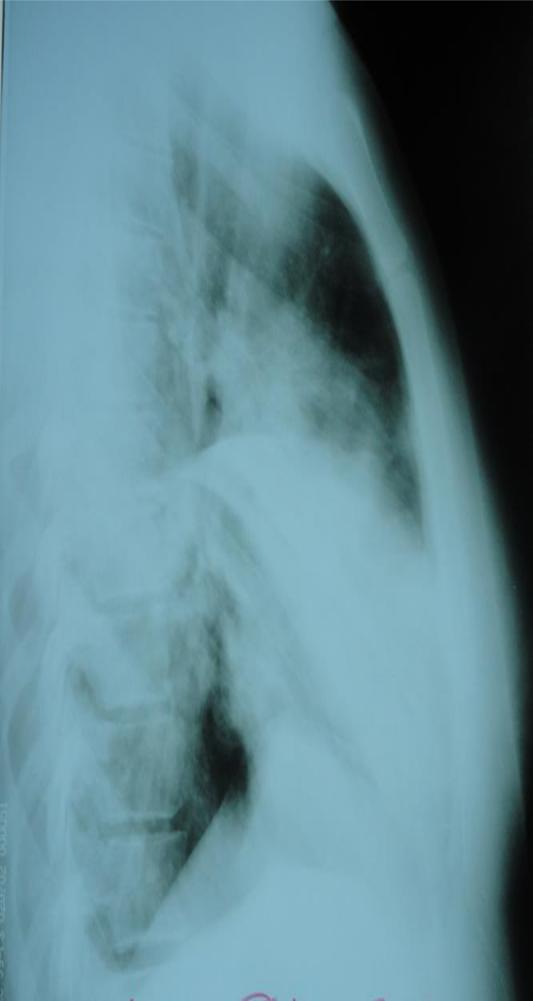

1.Предположите наиболее вероятный диагноз.

2.Обоснуйте поставленный Вами диагноз.

3.Составьте и обоснуйте план дополнительного обследования пациента.

4.Какова тактика лечения данного пациента, назовите препараты «стартовой» терапии и препараты резерва?

5.Какова тактика диспансерного наблюдения пациента после выписка из стационара?